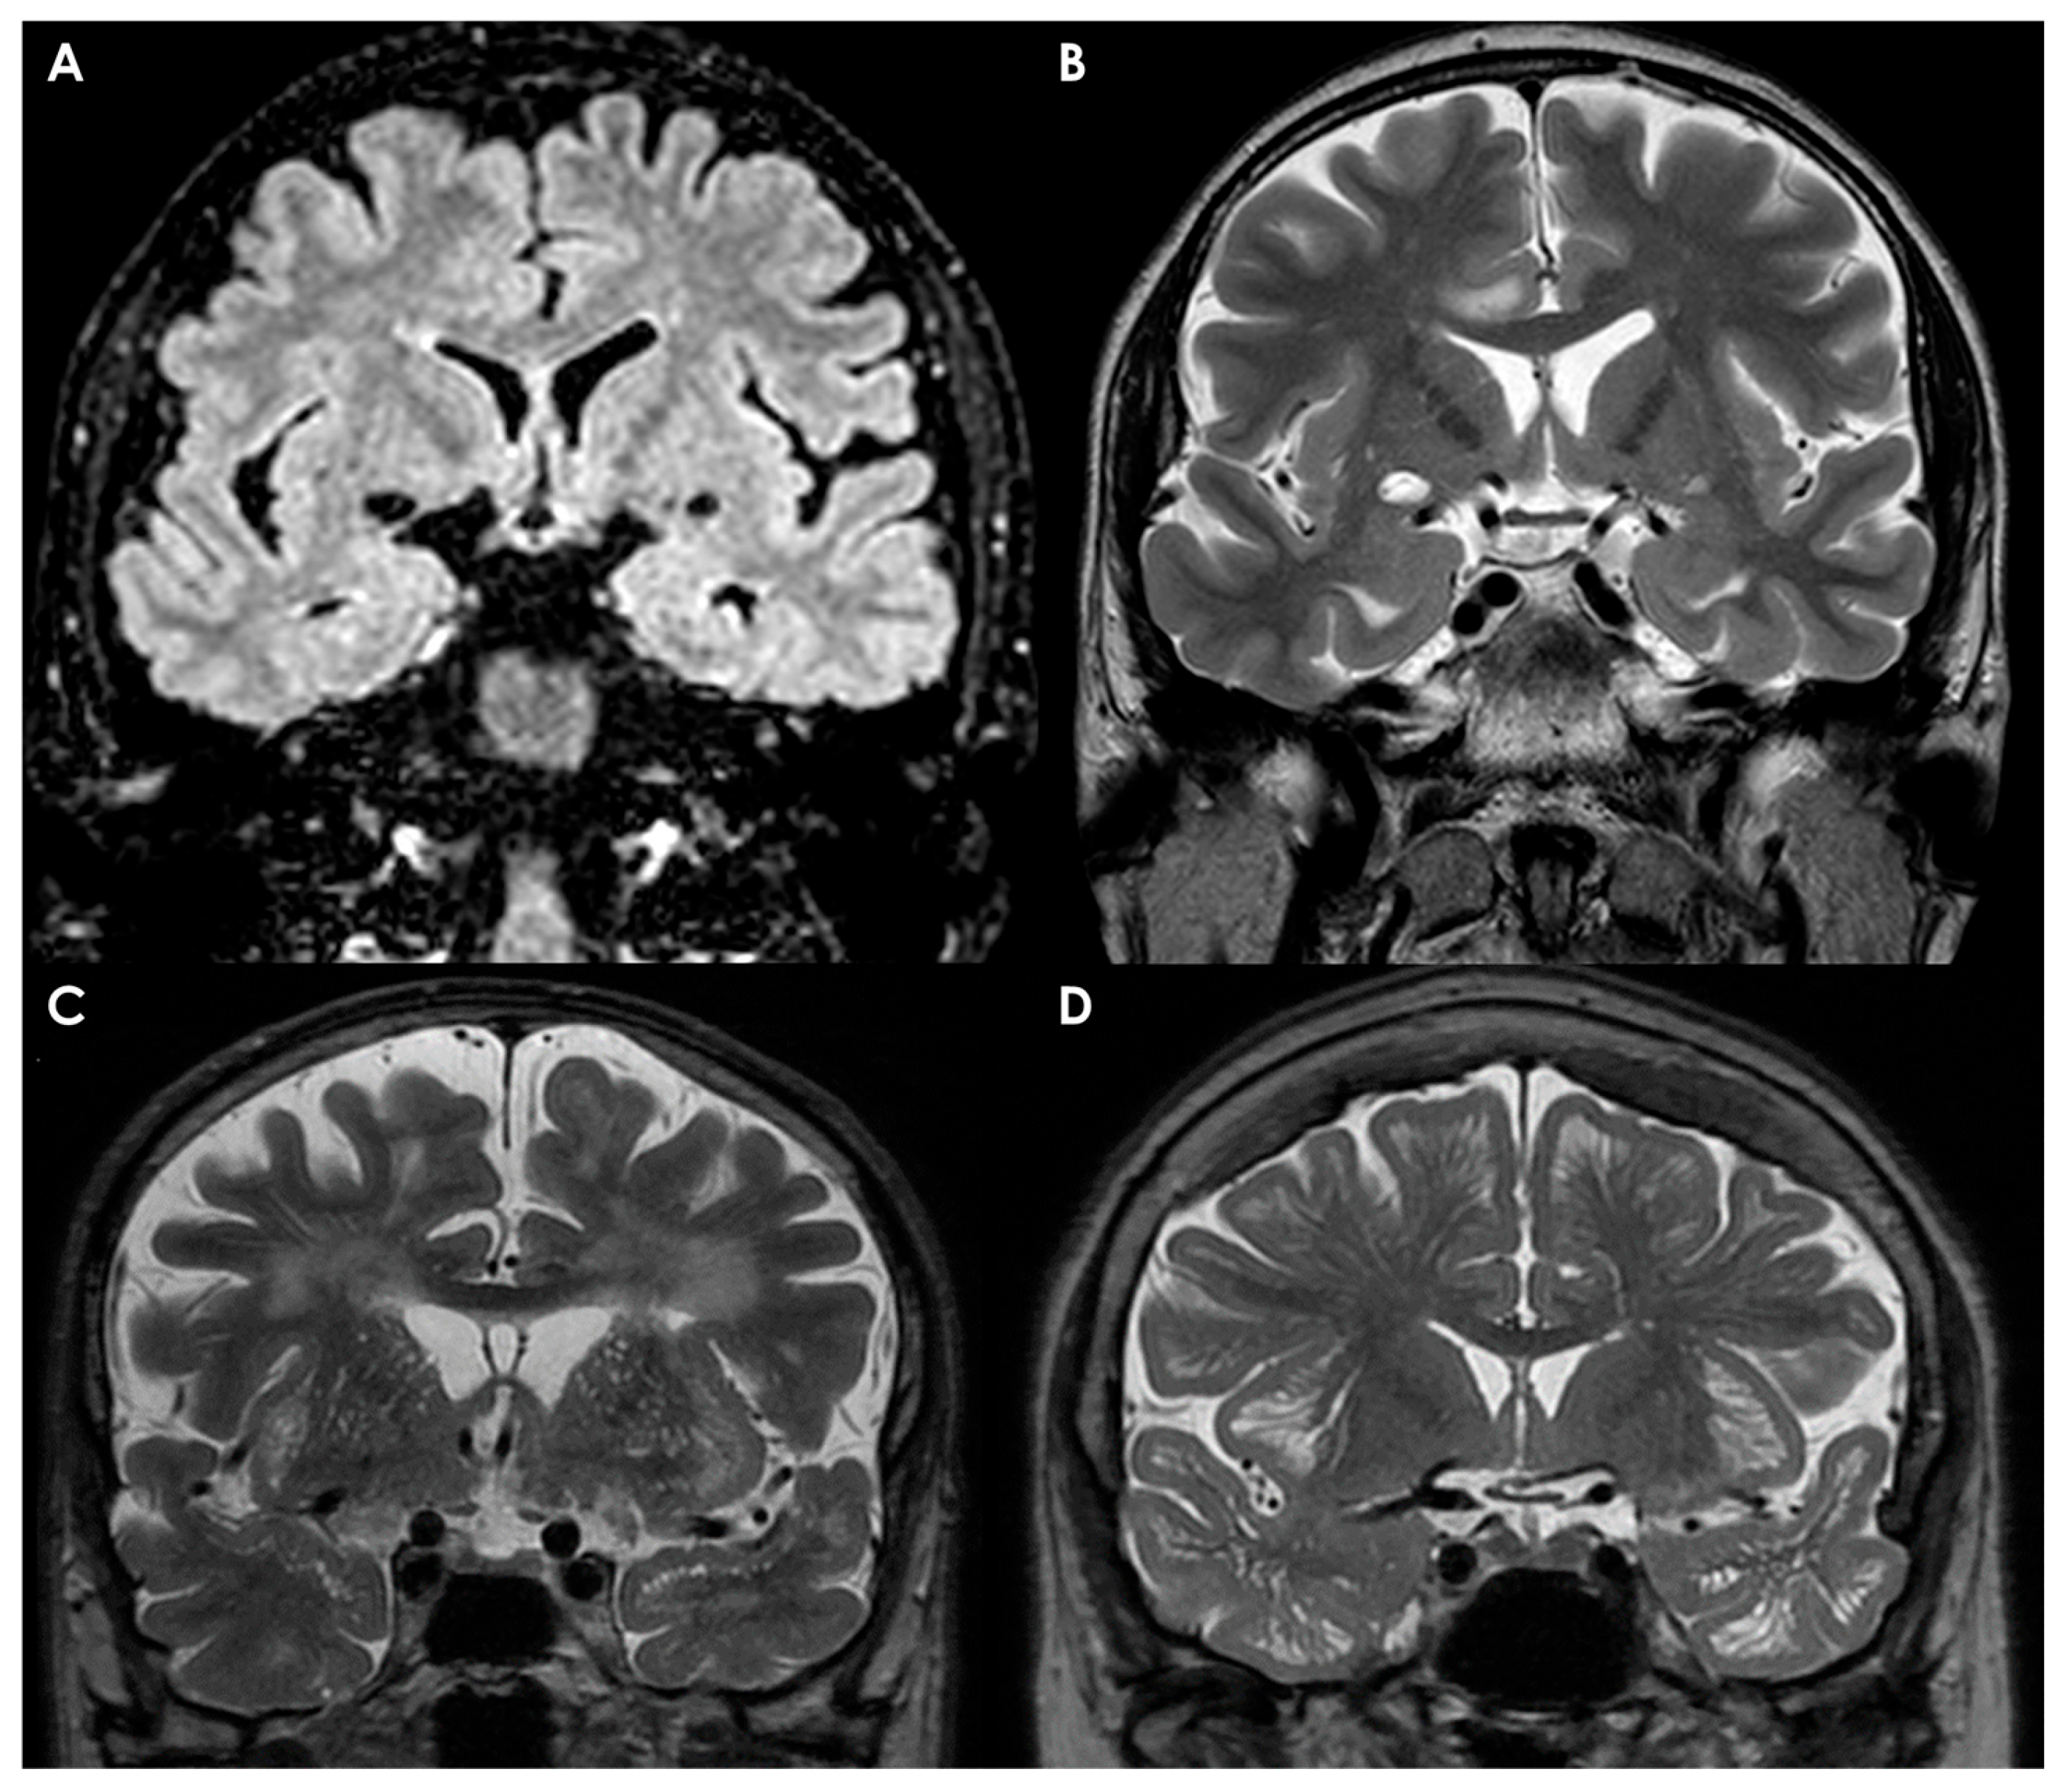

4.4. Perivascular Spaces

- Protein Aggregation: Abnormal protein aggregation, such as amyloid beta, may obstruct upstream cortical arteries, leading to interstitial fluid drainage issues and subsequent EPVS expansion [174].

- Brain Atrophy: Age-related brain atrophy creates a cavitation effect, pulling on tissue surrounding blood vessels and resulting in EPVS dilation [177].

- Blood–Brain Barrier Dysfunction: Damage to the blood–brain barrier (BBB) due to factors such as high blood pressure can increase BBB permeability, resulting in fluid leakage and EPVS enlargement [177].

Physiological Background of MRI Evaluation of Perivascular Spaces